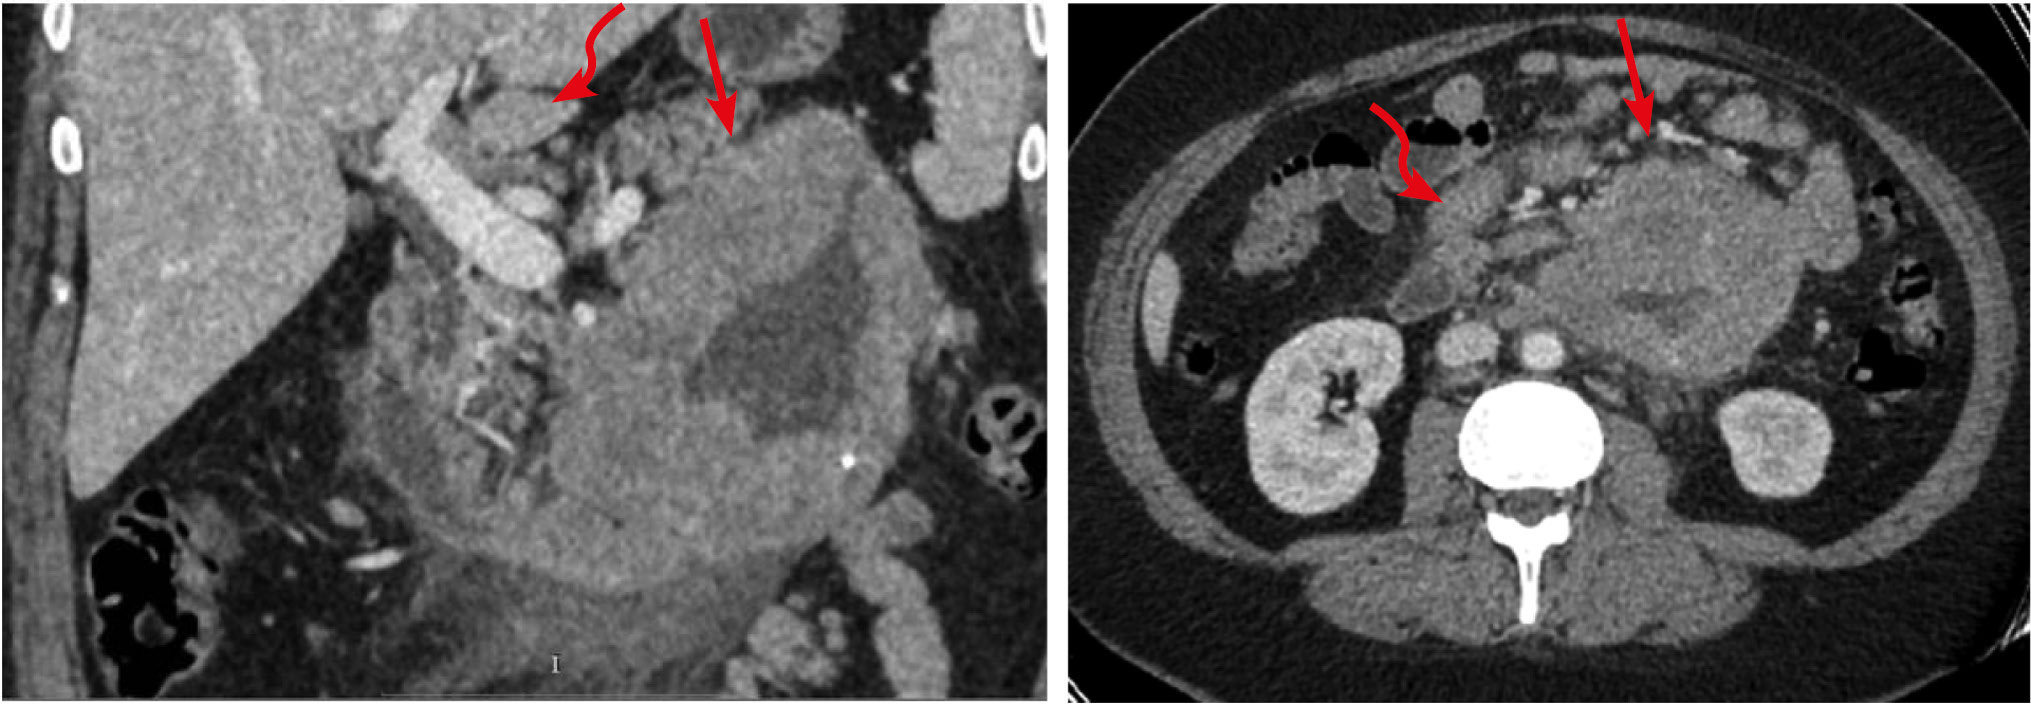

Рис. 7. Больная, 68 лет. МСКТ: первично-множественная синхронная лимфома (мезентериальная форма). Артериальная фаза контрастного усиления

Примечание. Определяются утолщения стенки желудка (стрелка), тонкой (обозначены овалом) и сигмовидной кишок. Четко визуализируется распространение лимфоидной инфильтрации на несколько рядом расположенных сегментов тощей кишки. Утолщение стенки кишки сопровождается умеренным и неравномерным расширением просвета. При контрастном усилении наблюдается повышенное контрастное усиление пораженных участков, в большей степени за счет слизистого слоя. Хорошо видны увеличенные лимфатические узлы в большом сальнике (пунктирная стрелка) и забрюшинном пространстве.

Раковая опухоль ТК — наиболее редкое заболевание. Аденокарциномы ТК встречаются в 50 раз реже, чем рак толстой кишки. Чаще заболевают мужчины в возрасте 60 лет и старше. В 50% наблюдений опухоль локализуется в двенадцатиперстной кишке. Тощая кишка поражается в 30% случаев. На долю локализации в подвздошной кишке приходится 20%, с большей частотой поражения дистального отдела. КТ-картина зависит от анатомического строения опухоли. Эндофитный рак прорастает во внутренние слои кишки на сравнительно малом протяжении и, располагаясь обычно на одной из стенок, первоначально не суживает просвет. Стенозирование наступает позже, когда опухоль распространяется циркулярно [22]. К опухолям эндофитного типа относится язвенно-инфильтративный рак, для которого характерно быстрое и агрессивное распространение в глубокие слои кишки и окружающие ткани. Язвенные новообразования достаточно глубокие и быстро проявляются кровотечением. Диффузно-инфильтративный рак образуется в подслизистом и слизистом слоях кишки. Такие опухоли не склонны к изъязвлениям и метастазируют относительно поздно. Иногда опухоли такого типа достигают больших размеров, и пораженный отдел кишки становится неподвижным и трудно дифференцируемым от больших карциноидов [23]. При КТ-исследовании, выполняемом по стандартной методике, выявить эндофитную опухоль, когда она занимает часть стенки кишки, сложно, поскольку для визуализации таких образований необходимо обеспечить тугое заполнение просвета кишки. В развернутых стадиях аденокарцином на КТ обнаруживалось циркулярное сужение просвета, протяженностью 50–100 мм. Переход пораженной части кишки в неизмененную характеризуется нависанием стенки. Престенотическое расширение и симптомы острой непроходимости не являются обязательными признаками рака ТК, но компенсированные формы непроходимости всегда присутствуют. При контрастном усилении ткань опухоли контрастировалась трансмурально, без разделения на слои, и была заметна неоднородность контрастного усиления (рис. 8).

Рис. 8. Больная, 58 лет. МСКТ: рак тощей кишки. Венозная фаза контрастного усиления (накануне выполнялось контрастирование просвета кишки per os, поэтому в просвете толстой кишки наблюдается остаточное контрастное вещество

Примечание. А — аксиальная томограмма, Б — сагиттальная реконструкция. Стенка тощей кишки на протяжении ~150 мм утолщена до 10 мм. Просвет кишки неравномерно сужен. Контрастное усиление стенки трансмуральное, изоденсивное с остальными отделами кишки (стрелки). Имеется уплотнение прилежащей части брыжейки за счет десмопластической реакции (пунктирная стрелка).

Для экзофитной формы рака характерен преимущественно узловой рост в просвет кишки. Визуально злокачественные опухоли такого типа напоминают гриб на широком основании. Иногда встречаются экзофитные опухоли блюдцеобразной и полипозной формы, широко прилежащие к стенке кишки и обтурирующие ее просвет [24]. При всех анатомических формах роста опухоли кишки в патологический процесс вовлекаются регионарные лимфатические узлы брыжейки: они уплотняются, их объем увеличивается, максимальный размер по ширине обычно достигает 10 мм и больше. В наших наблюдениях при контрастном усилении ткань опухоли контрастировалась трансмурально, неравномерно, интенсивность контрастного усиления не отличалась от таковой неизмененной стенки кишки (рис. 9). Экзофитные формы поражения сопровождались различной степени выраженности престенотическими расширениями просветов.

Рис. 9. Больная, 53 года. МСКТ: рак дистального отдела подвздошной кишки. Тонкокишечная непроходимость

Примечание. А — аксиальная томограмма, Б — сагиттальная реконструкция томограммы. Артериальная фаза контрастного усиления. В дистальном отделе подвздошной кишки на протяжении 10 см определяется экзофитное образование, суживающее просвет (стрелки). Опухоль трансмурально накапливает контрастный препарат. В тонком кишечнике имеются признаки компенсированной тонкокишечной непроходимости.